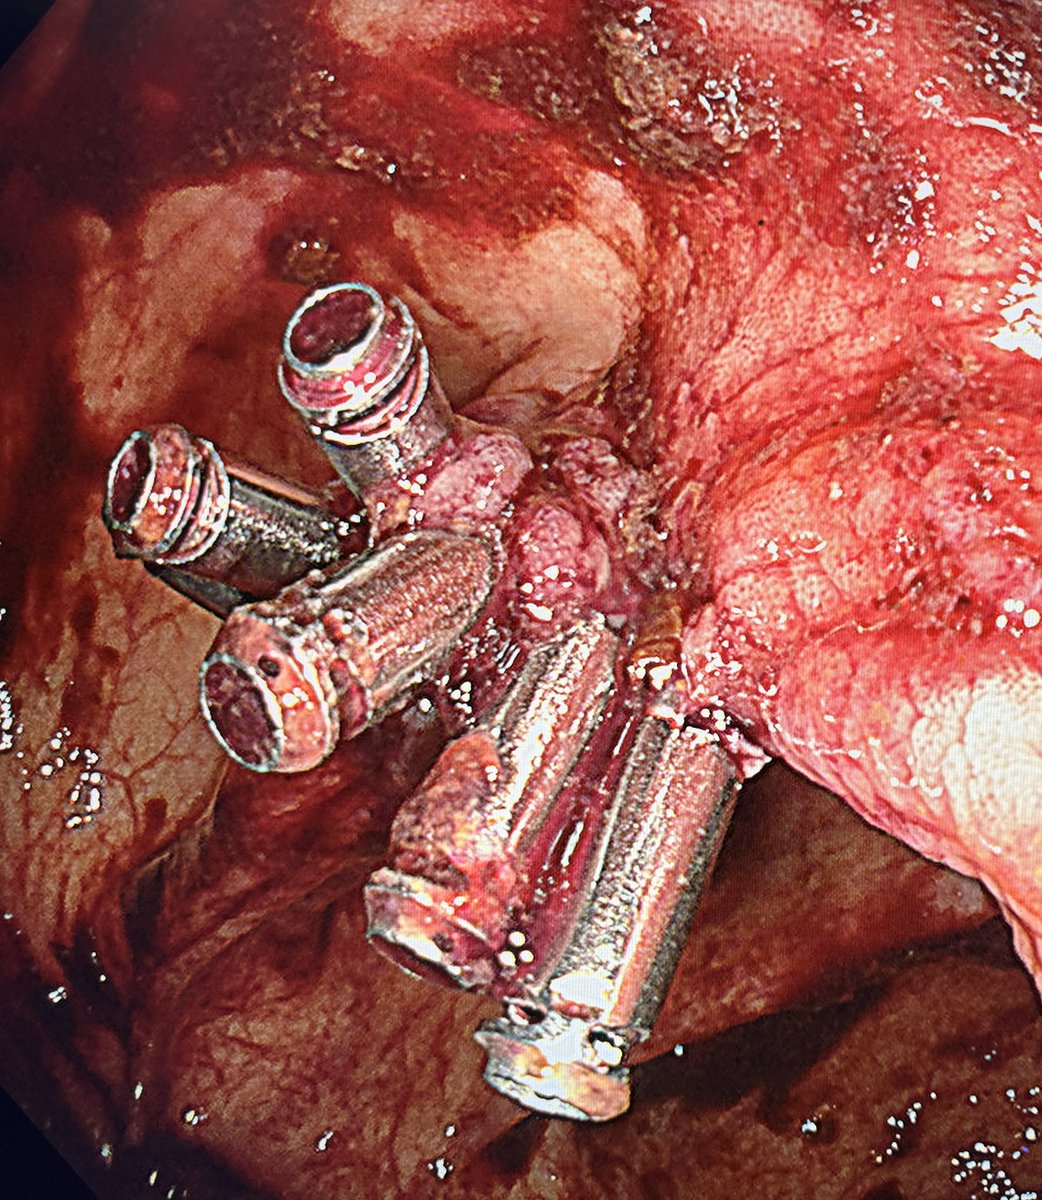

📢 March 2026 Issue #ACGCRJ 📷: Endoloop assisted hot snare polypectomy of a large brunner gland hamartoma in distal duodenum using colonoscope.🔦 🔗journals.lww.com/acgcr/pages/cu… @DushDahiya @DaniyalAbbasMD @AmCollegeGastro